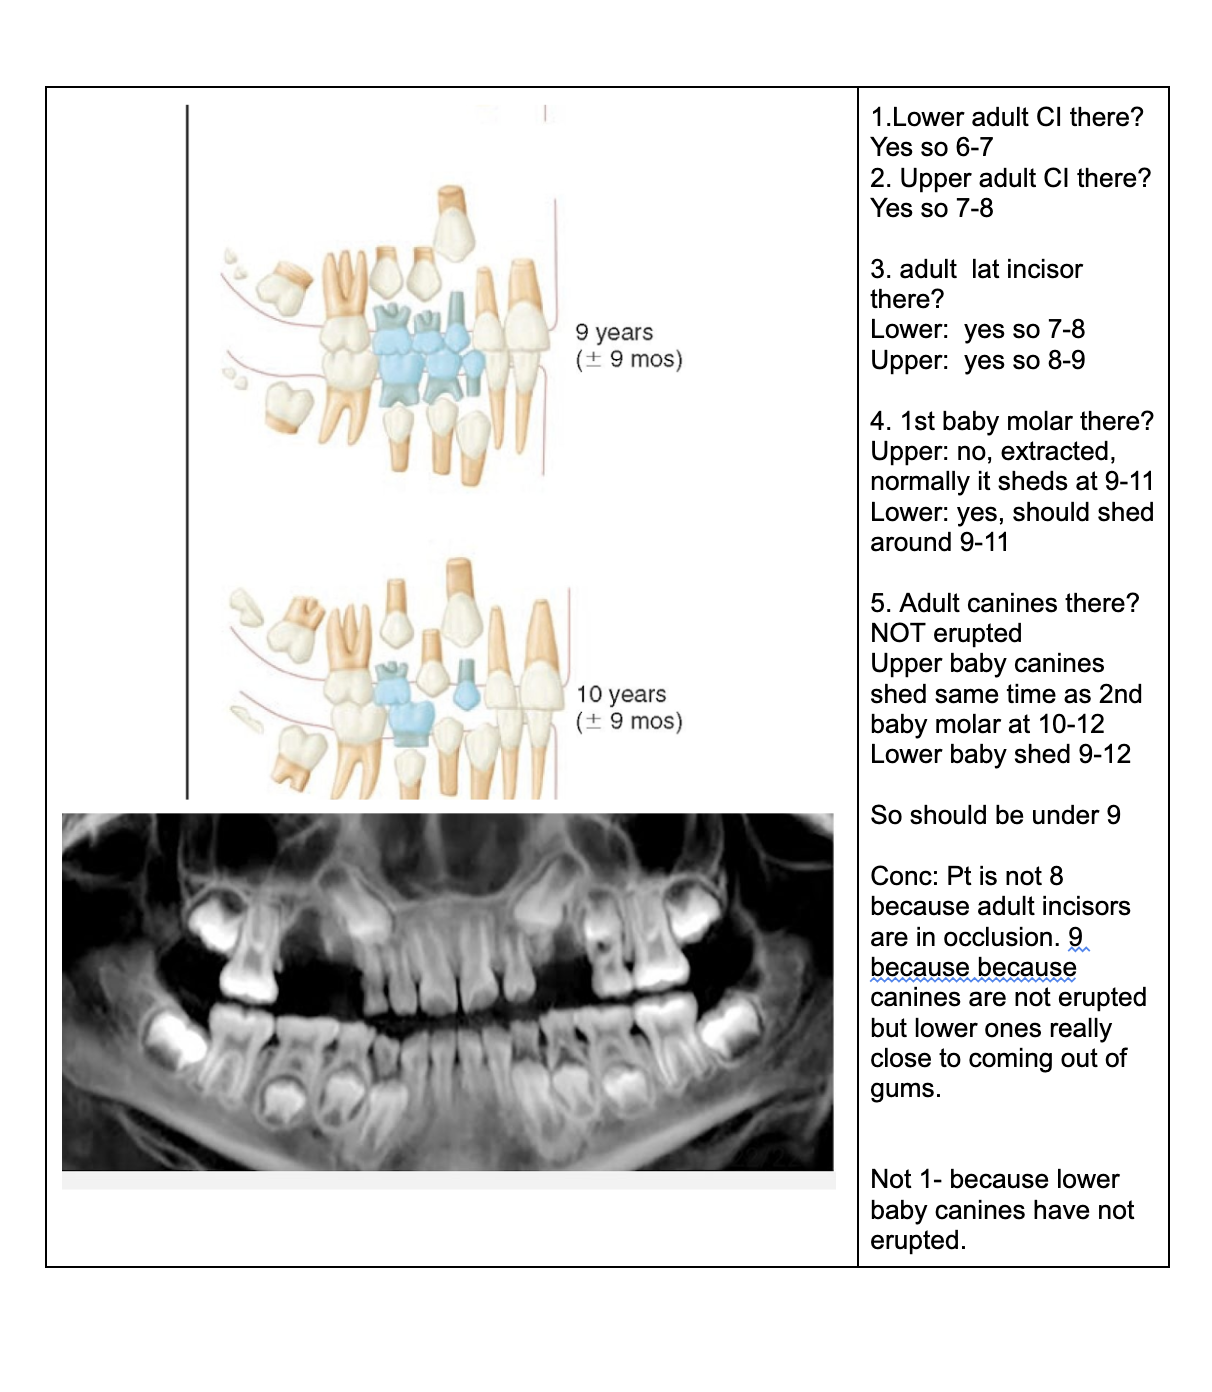

1.Lower adult CI there? YES. so def 6-7

1. Upper adult CI there (they normally erupt 7-8)? NO, baby ones should shed at 6-7.

Conc: pt. Is 6 y.o